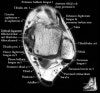

발목 관절의 MRI 단면 영상

- Axial section

Axial PD fat suppression evaluates the tendons and ligaments of the ankle particularly after acute/subacute injuries. It also is sensitive to talar dome osteochondral defects. Alternatively, a T2 sequence can be used to eliminate magic angle artifact that may occur as the tendons travel around the malleolar turns.

Tibiofibular ligaments

Lateral ankle ligaments

Deltoid and spling ligaments

Tendon(Achilles, Medial, Lateral, Anterior)